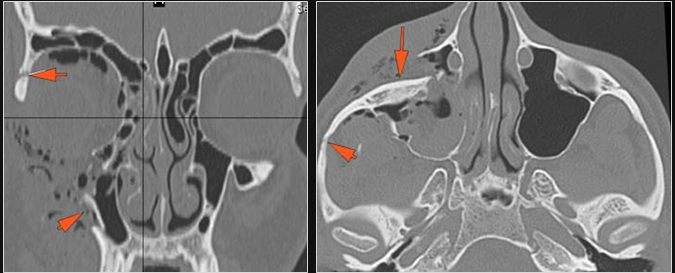

Possible facial, mandibular, orbital, and/or skull fractures, due to craniofacial trauma.Exam

Non-contrast CT of the maxillofacial region was obtained with 0.5-1.0 mm thick sections in the axial plane and reformatted 3D and/or in the coronal and sagittal planes and viewed interactively in 3 dimensions at the computer workstation.